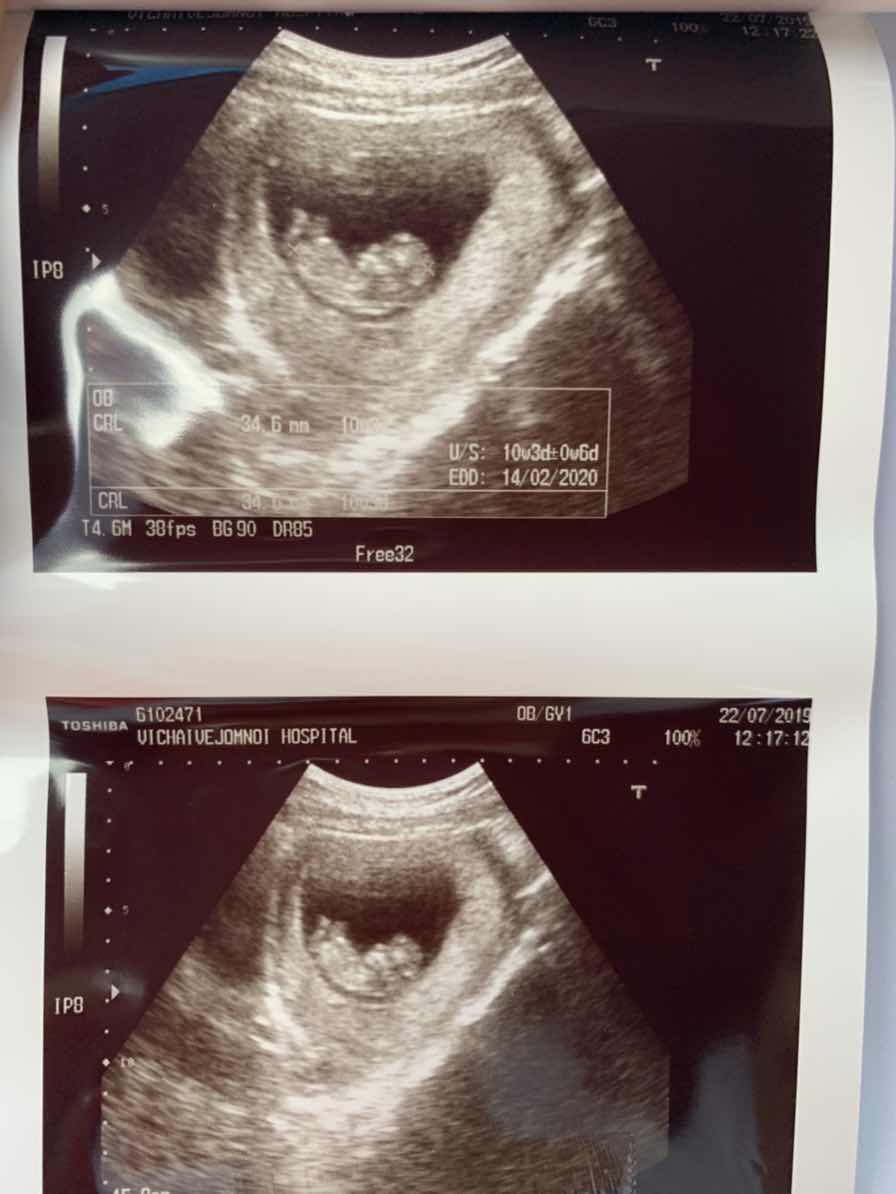

ตอน 10+3 w ค่ะ